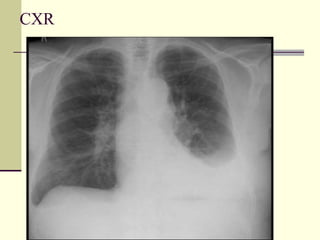

 CXR

CXR